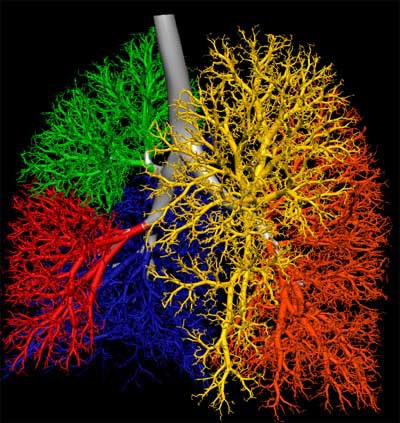

| Lungs of human (above) and sheep (below) are from a ventilation distribution model created in collaboration with Merryn Tawhai, Ph.D. from the University of Auckland in New Zealand. Lung, lobes and airway are located from CT data; lobes have not yet been delineated in sheep model below. The process uses the boundary conditions of the lung, lobe and airway tree to extend the branching patterns out by 7 to 9 generations in these images, though the model can be used to create a complete 23-generation airway tree. |